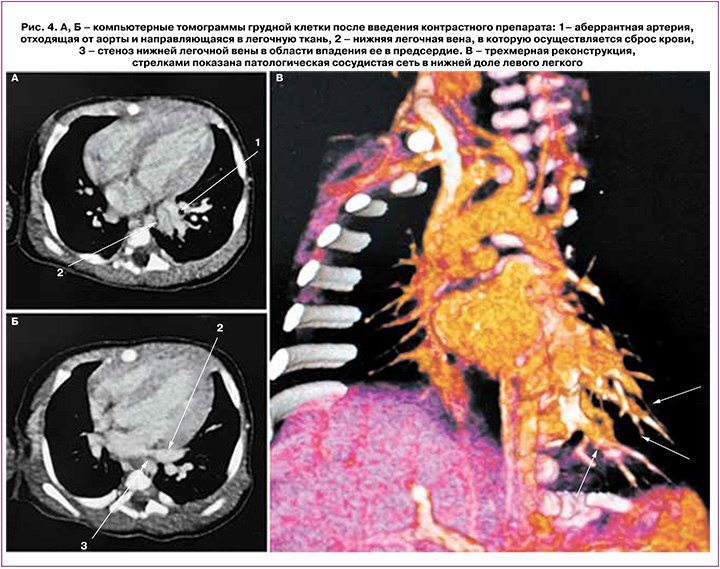

Проводилась местная терапия (асептические повязки на пораженные участки кожи, обработка эмолентами). На фоне проводимого лечения состояние кожи – с положительной динамикой, отмечались очаги гиперкератоза в области стоп, голеней, локтей (рис. 2), кистей. В возрасте 6 суток жизни отмечались воспалительные изменения в общем анализе мочи (лейкоциты покрывают все поля зрения), выставлен диагноз «Инфекция мочевыводящих путей». Проводилась антибактериальная терапия Амписидом в дозе 75–150 мг/кг/сут внутривенно струйно с положительным эффектом, завершена на 12-е сутки жизни. На 14-е сутки жизни состояние ребенка – с отрицательной динамикой за счет появления дыхательных нарушений в виде тахипноэ до 70/мин с втяжением подреберий, тахикардии до 170 /мин, грубого систолического шума с проведением на спину. Учитывая выявленные изменения, проводился контроль эхокардиографии (ЭхоКГ), по результатам которой определялась высокая легочная гипертензия – давление в правом желудочке составляло 85 мм рт. ст., отмечались увеличение и гипертрофия правого желудочка и умеренная гипертрофия левого желудочка сердца. Уровень N-терминального мозгового натрийуретического пропептида (NT-proBNP) составил 38 728 пг/мл. Клинические симптомы дыхательных нарушений сопровождались увеличением количества лейкоцитов в клиническом анализе крови до 19,6×109/л; по данным рентгенографии органов грудной клетки отмечались снижение прозрачности легочных полей с усилением легочного рисунка справа и признаки перегрузки правых отделов сердца. По результатам клинических данных был выставлен диагноз неонатальной пневмонии, в связи с чем проводилась антибактериальная терапия (ванкомицин 30 мг/кг/сут внутривенно капельно, сульперазон 80 мг/кг/сут внутривенно капельно в течение 7 дней). Учитывая клинические признаки сердечной недостаточности, дилятационной кардиомиопатии, сохраняющиеся признаки легочной гипертензии, проводилась диуретическая терапия (верошпирон 3,5–4,0 мг/кг/сут, фуросемид 1–2 мг/кг/сут перорально); на 26-е сутки жизни назначена вазодилатирующая терапия (силденафил-кардио (Ревацио) 1 мг/кг/сут перорально), однако недостаточность кровообращения сохранялась. По данным ЭхоКГ отмечались кардиомегалия, легочная гипертензия – давление в правом желудочке составляло 60 мм рт. ст. На 33-е сутки жизни с диагностической целью выполнена мультиспиральная компьютерная томография органов грудной и брюшной полости с внутривенным контрастированием, выявлен порок развития левого легкого – интралобарный секвестр нижней доли левого легкого с выраженным сбросом крови по аномальному сосуду в венозное русло малого круга кровообращения, расширением нижней легочной вены слева и ее стенозом в области впадения в предсердие; гипоплазия левой легочной артерии; тромбоз нижней полой вены с частичной реканализацией и формированием паравертебральных сплетений (рис. 3, 4).

Таким образом, тяжесть состояния ребенка была обусловлена наличием врожденного порока развития левого легкого с формированием сосудистого шунта из аорты в нижние легочные вены, что явилось причиной легочной гипертензии, перегрузки камер сердца и сердечной недостаточности. Учитывая значительный объем шунтируемой крови, признаки легочной гипертензии, перегрузки камер сердца и сердечной недостаточности ребенок на 39-е сутки жизни был переведен в отделение хирургии новорожденных, где была проведена торакоскопическая перевязка аномального артериального сосуда нижней доли левого легкого. В послеоперационном периоде состояние ребенка – с положительной динамикой, отмечалось уменьшение размеров камер сердца, снижение давления в системе легочной артерии (расчетное давление в правом желудочке по НТК 40–44 мм рт. ст., при системном 118/66 мм рт. ст.). Уровень NT-proBNP в крови снизился до 977,8 пг/мл. На 40-е сутки жизни ребенок переведен в отделение патологии новорожденных и недоношенных детей и на 48-е сутки выписан домой в удовлетворительном состоянии. При ЭхоКГ перед выпиской отмечалось открытое овальное окно, небольшое утолщение миокарда обоих желудочков, без нарастания в динамике, небольшое увеличение левых отделов сердца, умеренная гипоплазия левой легочной артерии, насосная и сократительная функции миокарда сохранены, данных за легочную гипертензию нет.